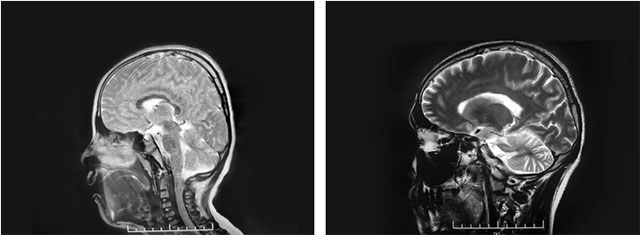

上海藍十字腦科醫(yī)院神經(jīng)外科6A病區(qū)主任侯增欣主任在詳細了解文文的病情病史后,對患兒的頭圍進行測量,結果為51cm,略小于該年齡段頭圍的參考最低值53cm。頭型從側面看則呈明顯的“橫窄豎高”,呈“尖頭”形。隨后,通過對文文顱骨CT的三維重建,可見其冠狀縫、矢狀縫等顱縫已融合,據(jù)此診斷為顱縫早閉。

▲ 患兒頭型(左)與正常頭型(右)對比